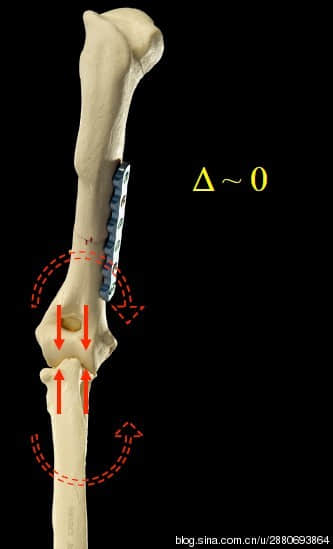

由于有了上述方法也算有一定的效果,为了避免上述方法带来的二次骨折或者植入物失败的风险,有聪明的兽医师发展了另外一种相对安全而又可以使肘关节两个髁受力均匀的办法。就是在打断肱骨之后进行外旋,使之受力均匀。这不失为一个好办法,但却会使动物迈步的动作变得比较畸形(如上图)。无论用上述2个方法的那一个,都需要折断肱骨这个很大的骨头,所以上述方法有其天然的风险不可避免。所以有的兽医师右发展出别的办法。

而欧洲和北美的一些最新的研究认为,改变尺骨力学方向会得到比较不错的效果。于是发展出了PAUL技术(proximal abducting ulnar osteotomy)。从目前的研究来看,PAUL取得了不错的效果。几乎全部使用了PAUL手术的狗都会得到不同程度的改善。所以,我和很多欧洲的骨科宠物专家一样,接受了PAUL手术认证,成为了PAUL的支持者。